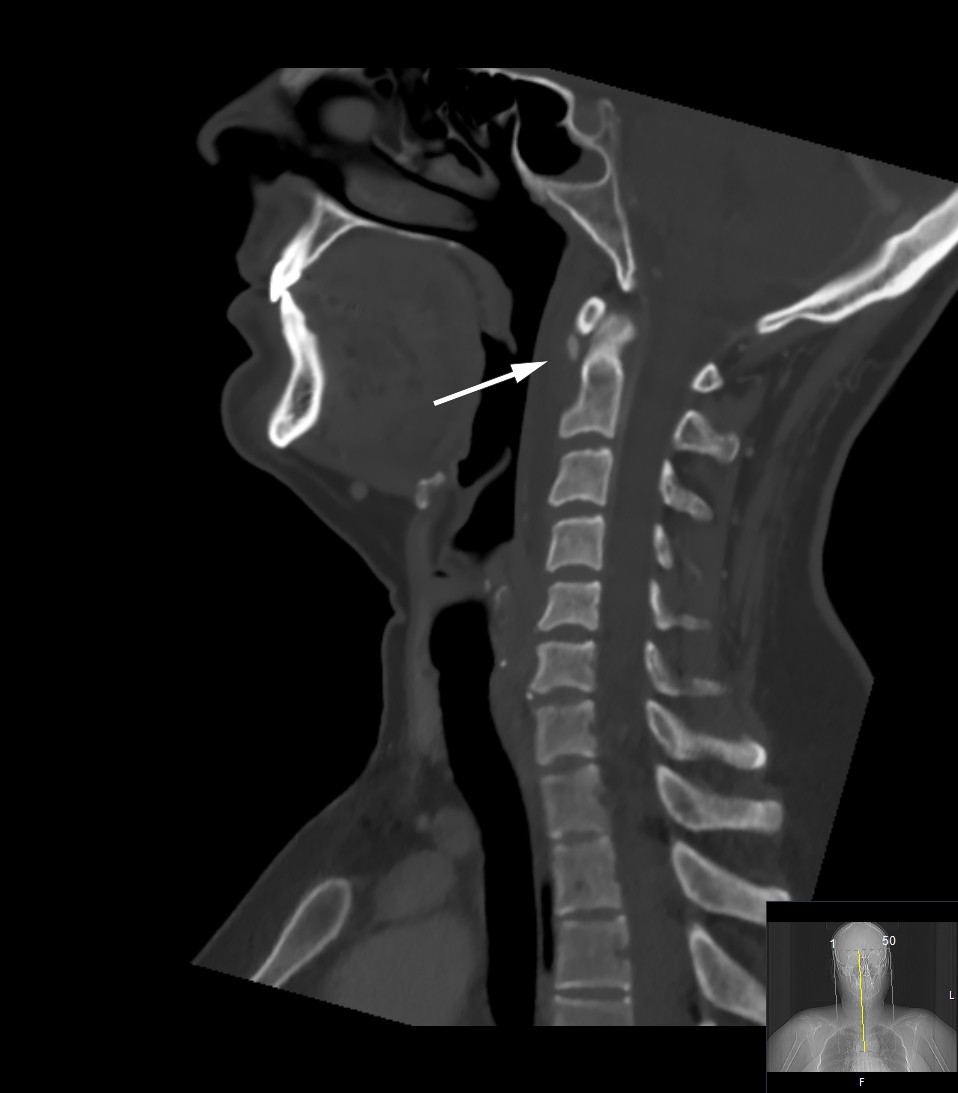

Grunnet mistanke om retrofaryngeal abscess ble pasienten henvist til CT-undersøkelse av collum med intravenøs kontrast, som viste et smalt væskesjikt retrofaryngealt og en liten, avrundet forkalkning ved nedre kant av fremre atlasbue (figur 1). Det var ingen kontrastoppladning rundt væskesjiktet, gasslokulamenter eller forstørrete lymfeknuter, som man radiologisk ville forvente ved abscess.

Tilstanden kan imitere infeksiøse tilstander som retrofaryngeal abscess og spondylodiskitt. Som denne kasuistikken viser, er bildediagnostikk essensielt for å stille diagnosen. Gullstandarden er CT av collum med intravenøs kontrast, som fremstiller de patognomoniske forkalkningene i longus colli-senen i de øvre fibrene i nivå med C1–C2 (1–4) – som også ble påvist hos denne pasienten (figur 1).

Mengden kalk kan variere og korresponderer ikke med grad av inflammasjon (2). Det kan foreligge sekundære inflammatoriske forandringer som væske retrofaryngealt og ødem i det prevertebrale bløtvevet, som påvist på både CT og MR hos denne pasienten (figur 1 og 2). Ved retrofaryngeal abscess vil man forvente kontrastoppladning rundt væskesjiktet, eventuelt gasslokulamenter og forstørrete lokale lymfeknuter, i motsetning til ved kalsifiserende tendinitt, hvor dette er fraværende (2, 4). Hos denne pasienten ble det likevel gitt antibiotika, da en infeksiøs prosess ikke kunne utelukkes helt. Antibiotikabehandlingen ble riktignok seponert, da pasientens symptomer gikk raskere tilbake enn man ville forvente ved infeksjon, noe som styrket mistanken om kalsifiserende tendinitt.